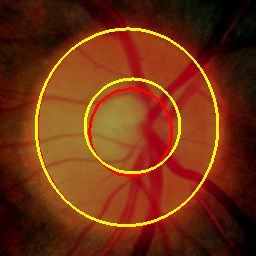

Medical image segmentation is a primary task in many applications, and the accuracy of the segmentation is a necessity. Recently, many deep learning networks derived from U-Net have been extensively used and have achieved notable results. To further improve and refine the performance of U-Net, parallel decoders along with mask prediction decoder have been carried out and have shown significant improvement with additional advantages. In our work, we utilize the advantages of using a combination of contour and distance map as regularizers. In turn, we propose a novel architecture Psi-Net with a single encoder and three parallel decoders, one decoder to learn the mask and other two to learn the auxiliary tasks of contour detection and distance map estimation. The learning of these auxiliary tasks helps in capturing the shape and boundary. We also propose a new joint loss function for the proposed architecture. The loss function consists of a weighted combination of Negative likelihood and Mean Square Error loss. We have used two publicly available datasets: 1) Origa dataset for the task of optic cup and disc segmentation and 2) Endovis segment dataset for the task of polyp segmentation to evaluate our model. We have conducted extensive experiments using our network to show our model gives better results in terms of segmentation, boundary and shape metrics.